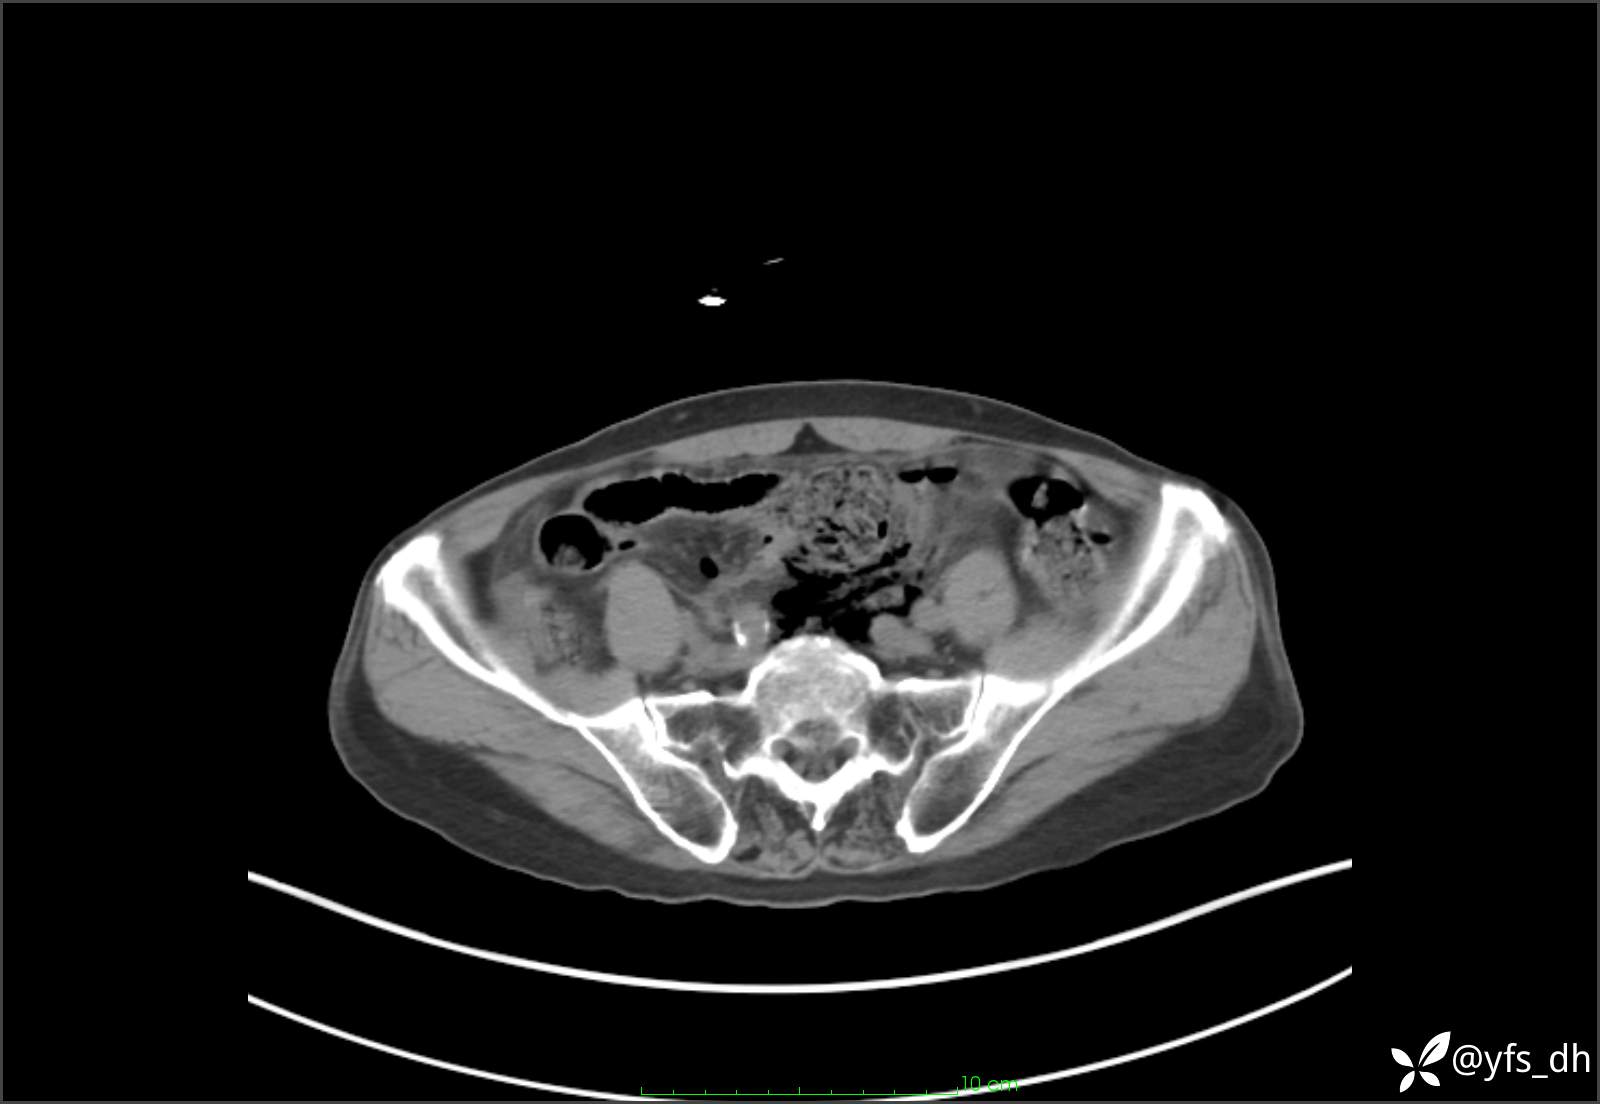

1.简要病史:患者4天前突发上腹部疼痛不适,但可以忍受。3小时前饭后突然加重,不能忍受后就诊。

2.简要手术记录:术中见腹盆腔大量肠液及粪便,乙状结肠中下段见一约3cm的破口。